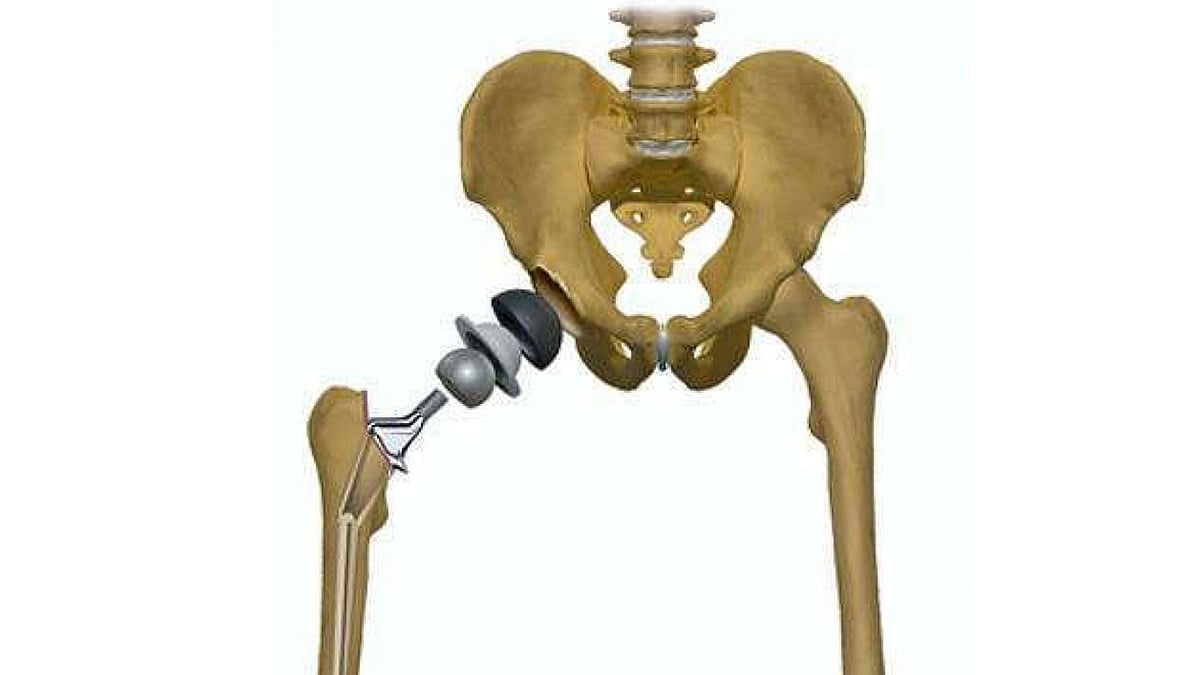

Замена обоих тазобедренных

Замена обоих тазобедренных 111 фотографий